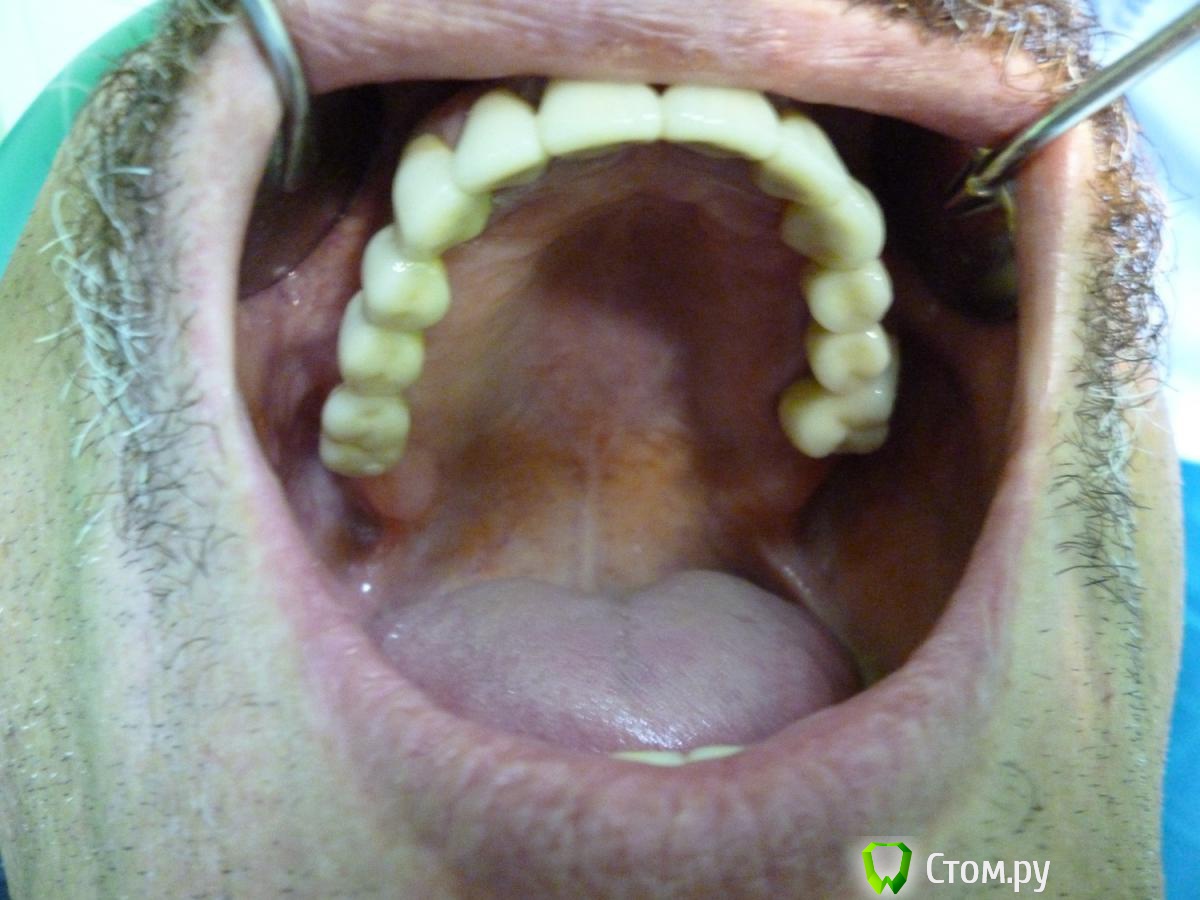

Troy Опубликовано 28 апреля, 2014 Поделиться Опубликовано 28 апреля, 2014 Вот такой рекольчик субпериостальников 5 лет прошло. Только камнями за НЧ кидать не надо . Это все таки моя глубокая молодость и за 5 лет мои взгляды сильно поменялись :). На синус пациент был категорически не согласен (интернет виноват),а хотел несъем2009 год2014 год. Жалоб нет. Так это выглядит сейчас. Ленты необнажены. Пардон за плохие фотки - фоткал на колегину мыльницуХотелось бы услышать Ваши комменты. 1 5 Ссылка на комментарий

Troy Опубликовано 28 апреля, 2014 Автор Поделиться Опубликовано 28 апреля, 2014 В третьем сегменте кость у имплантов ушла почти на 1/2, 2.7 удалять. Фото плохие, в Области 2.5 похоже свищ, резьба винтов тридцатой стороны выступает в полость рта и все в камнях. Мало?27 - его любимый зуб, он отказался его удалять еще 5 лет назад, пошли на поводу, пролечили покрыли, пока небеспокоит. В обл 25 свища нет, красное пятно артефакт на снимке фото плохие. Камней у него нет. Проблеммы в 3 сегменте действительно присутствуют. Но цель была показать СПИ.Извините что разачаровал .... :( А не новокузнецкие ли это "шедевры" ?Нет 1 1 Ссылка на комментарий

Troy Опубликовано 30 апреля, 2014 Автор Поделиться Опубликовано 30 апреля, 2014 уже одним синуслифтингом не обойтисьНе могли бы вы поподробнеее изложить свои мысли по этому поводу. А то как то уж совсем коротко получается... значит показалось Так точно! Вы действительно считаете что это хорошо?Я разве где-то сказал что это хорошо ??? Я попытался показать исход и что бывает с СПИ в средних сроках функционирования. Тем более что они пока еще в функции. Форум это же не только выставка всего самого лучшего. Или у вас боков не бывает? Не всегда получается быть умным и красивым... Извините что не поняли мои намерения. Я этим не похвастаться хотел. Да и на форуме не одного СПИ нет. Или поиск не работает... в третьем секторе еще до установки формирователя кость уже убежала от импланта?через 5 лет кость убежала вездеВсе правильно, как в воду смотрели. Как Вы думаете без реимплантации получиться в этом секторе. Хотя бы чисто теоретически...Очень интересно было бы Ваше мнение по поводу дальнейшей реабилитации ВЧ Заранее спасибо 1 Ссылка на комментарий